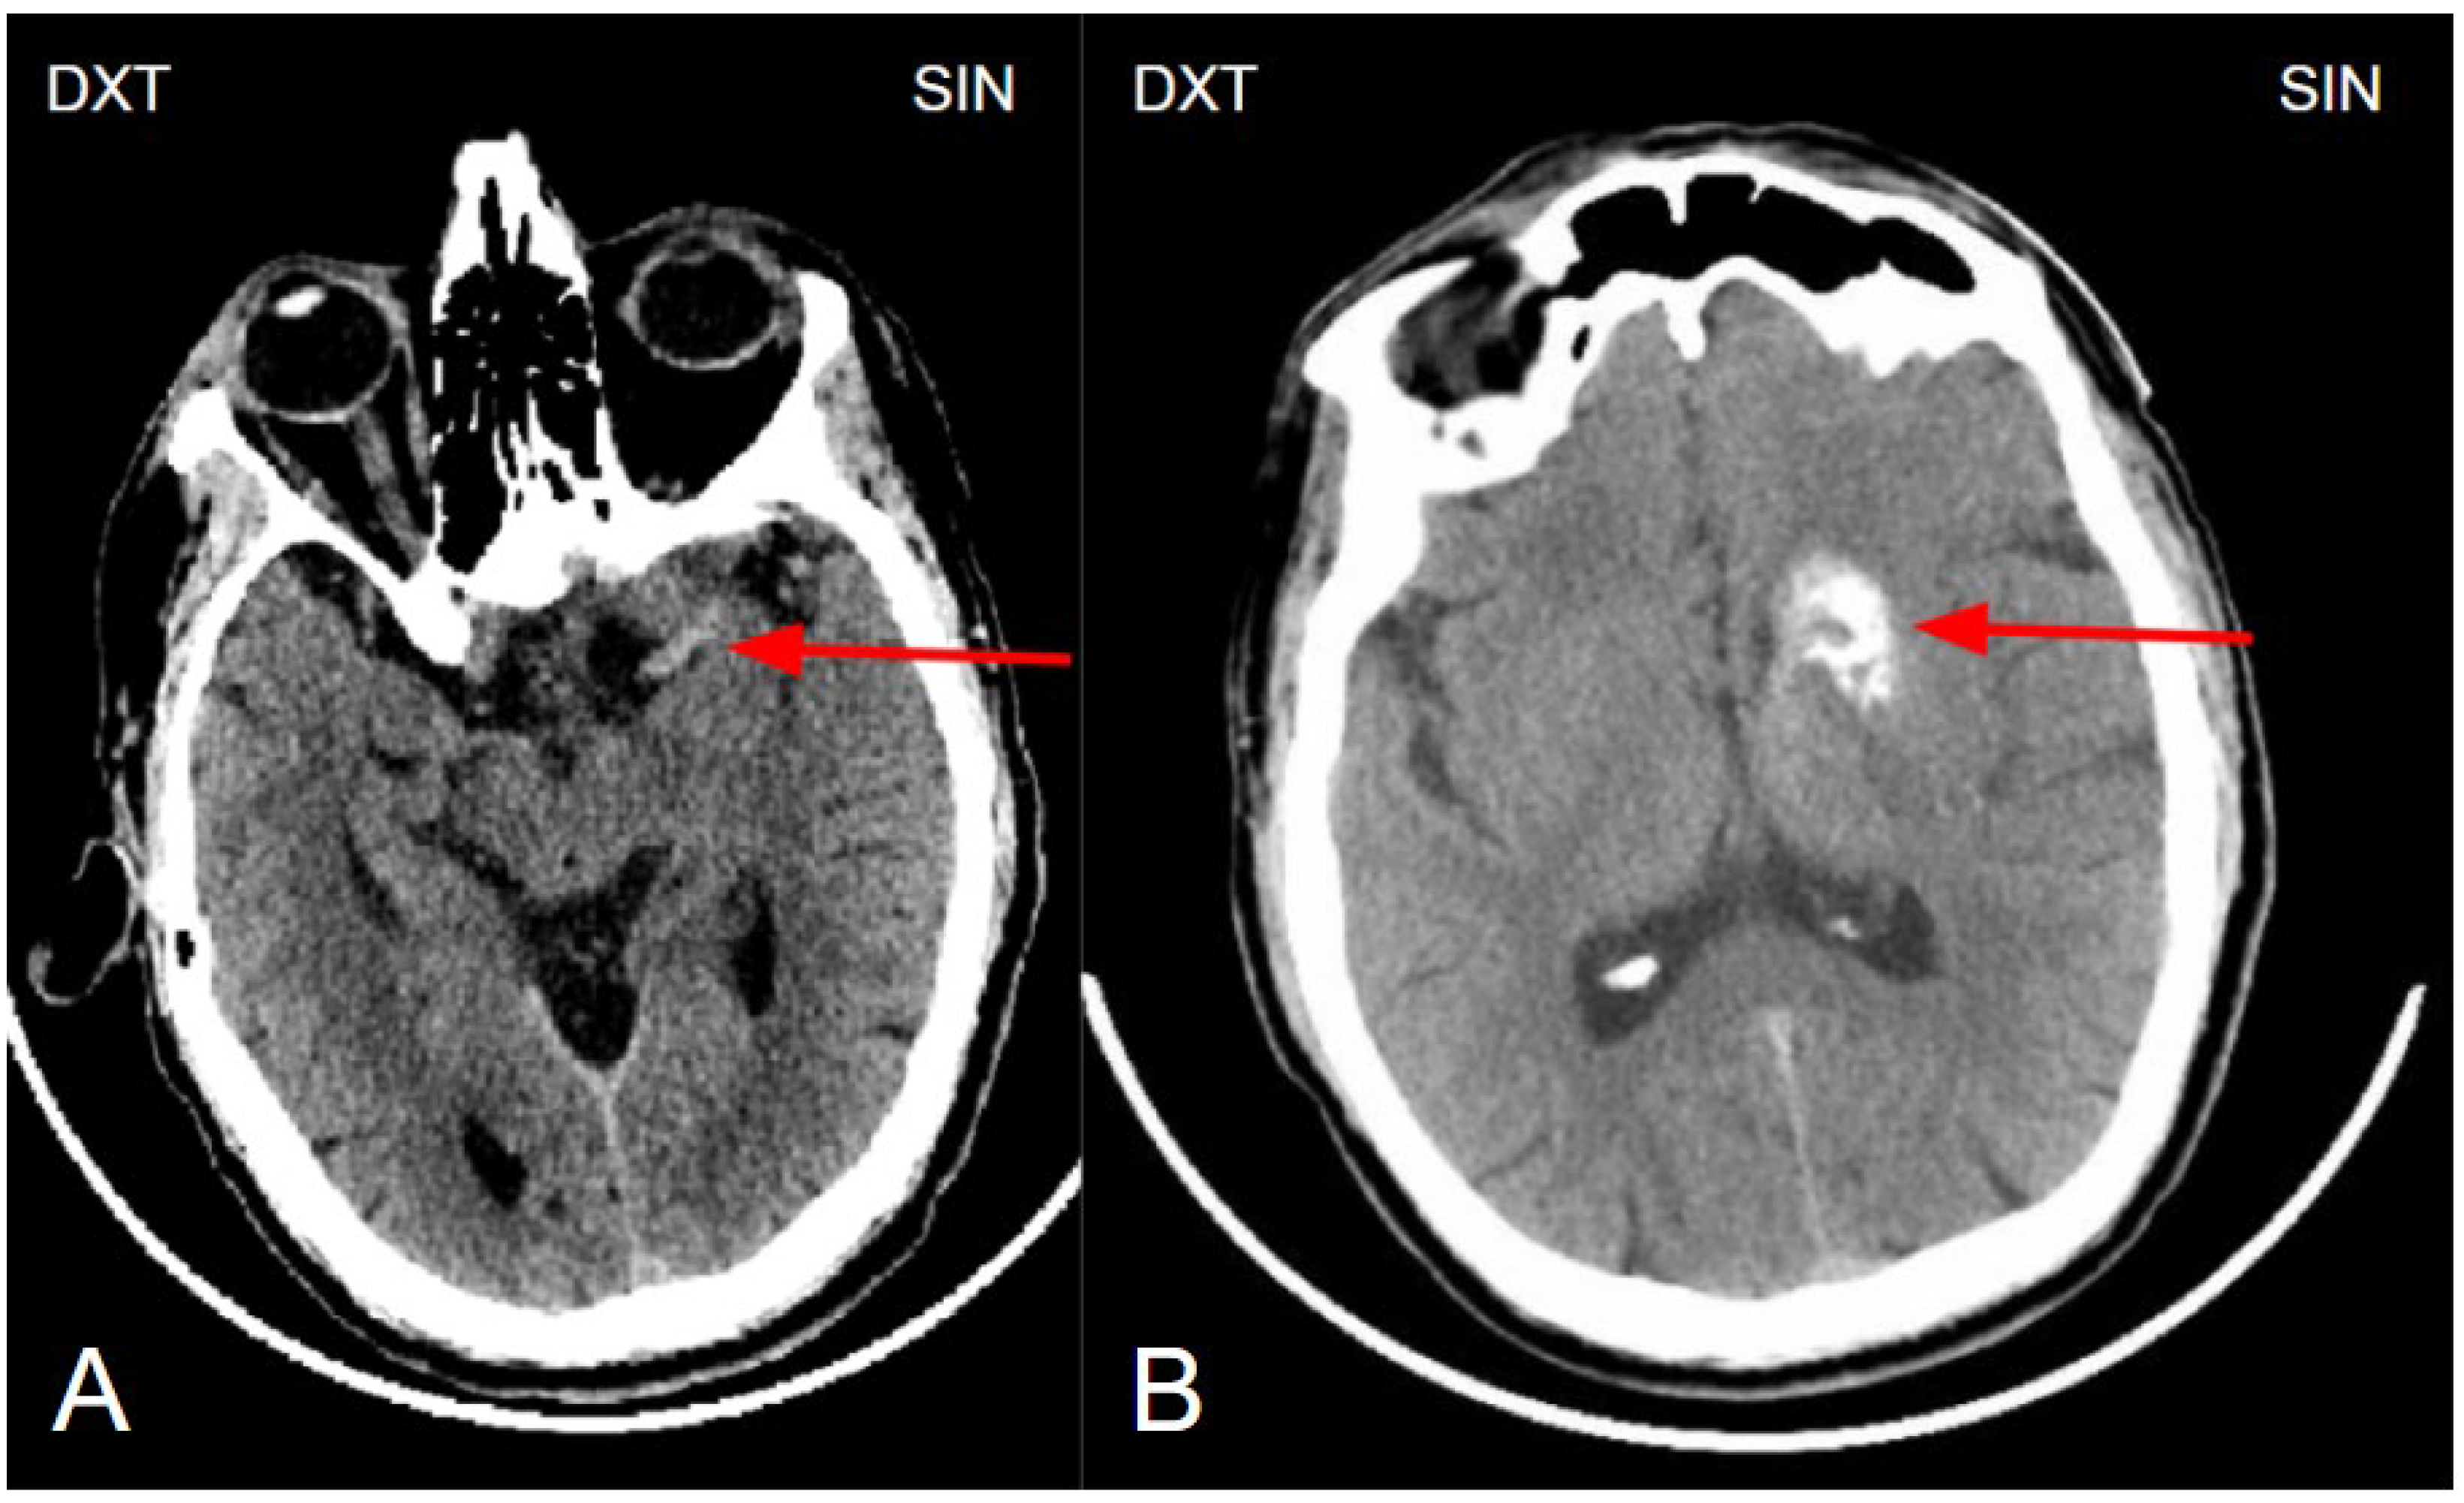

Figure 1. (A) Non enhanced computed tomography of the brain showing a hyperdense artery sign, arteria cerebri media sin. M1 segment (red arrow). The hyperdense artery sign typically indicates acute thrombosis, especially in the presence of corresponding neurological symptoms. (B) Non-enhanced computed tomography of the brain at the basal ganglia level shows unilateral basal ganglia calcinosis, predominantly in the caput nuclei caudati and nucleus lentiforme (red arrow), without perifocal edema or mass effect, suggesting changes of a more likely benign nature.

The initial NECT radiological findings did not provide a definitive diagnosis and did not show any signs of acute ischemia. Considering the patient’s clinical presentation and initial NECT findings, further investigation with CT angiography was conducted. An acute occlusion of the M2 segment of the left middle cerebral artery (MCA) was identified, accompanied by leptomeningeal collaterals extending to the left brain hemisphere with a Tan collateral score of 3 (Figures 1, 2, 3 and 4). A subsequent perfusion CT was performed revealing an extensive hypoperfusion zone predominantly consistent with a penumbra-type lesion (Figure 5). No hemorrhage was observed. The emergency department radiologist and neurologist raised concerns regarding the possibility of an acute ischemia combined with primary neoplastic tumour and calcification of the basal ganglia, potentially a high- grade oligodendroglioma. Therefore, an acute thrombolytic therapy with intravenous thrombolysis was contraindicated. Thrombolysis is typically constrained to a standardized 4.5-hour window to optimize reperfusion outcomes and minimize the risk of ischemia-reperfusion injury [24,25]. The patient was subsequently admitted to the Stroke Unit for further evaluation and management.

The next day, a neuroradiologist reviewed a control followup NECT, that demonstrated an ischemic lesion localized to the left insula, predominantly involving the left parietal lobe and the superior gyrus of the left temporal lobe (Figure 1). Additional radiological findings included a hyperdense artery sign, characteristic of acute thrombosis, and basal ganglia calcification on the left side, warranting further investigation to clarify the underlying aetiology. Subsequently MRI of the brain was conducted, which also revealed ischemic signs, as well as unilateral basal ganglia calcification (Figure 6). Digital subtraction angiography (DSA) was performed to clarify reasons for unilateral basal ganglia calcifications, and it confirmed the presence of a developmental venous anomaly (Figure 7).